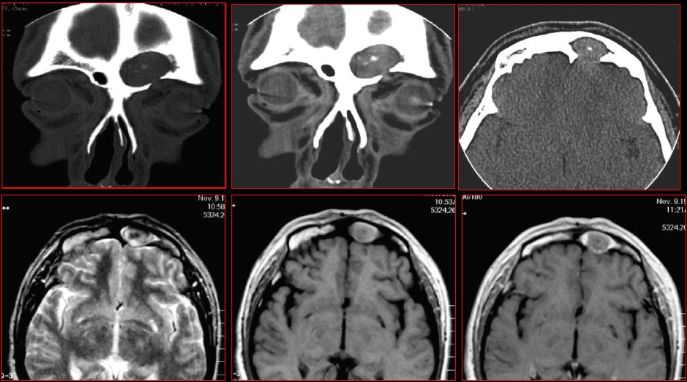

鼻窦炎—骨质改变

鼻窦炎—骨质增生

鼻窦炎—骨质增生及脑膜炎

额窦脓囊肿